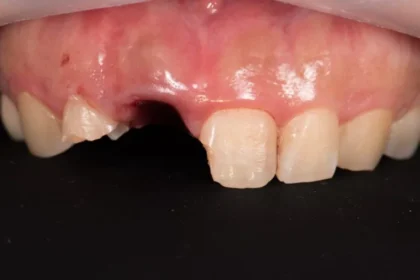

前歯などの審美性が求められる

インプラントもお任せください

治療前

治療後